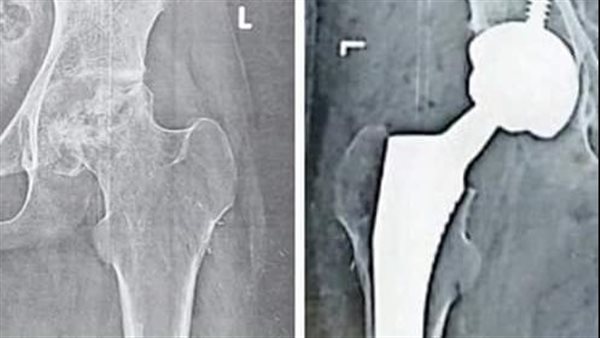

أعلنت الهيئة العامة للرعاية الصحية نجاح جراحة دقيقة لتغيير مفصل كامل للفخذ لا أسمنتي ذو رأس سيراميكي، لتستعيد المريضة حركة المفصل الطبيعية، وإعادة طول الطرف السفلي الأيسر مرة أخرى، وذلك باحترافية عالية.

وأكدت هيئة الرعاية الصحية، أن فريق جراحة العظام بمجمع الشفاء الطبي بمستشفى التضامن ومستشفى المبرة بورسعيد، تمكن من إعادة الأمل لطفلة تبلغ من العمر 16 عامًا ، في ممارسة حياتها بشكل طبيعي كانت بعدما كانت تعاني من تآكل تام برأس عظمة الفخذ، وذلكونتيجة تعرضها لحادث وعمليات متتالية مع كسر بعنق عظمة الفخذ وقطع بالإمداد الدموي المغذي لرأس العظمة في مكان المفصل، مما أدى الى ضمور برأس العظمة وقصر طول بالطرف السفلي الأيسر.